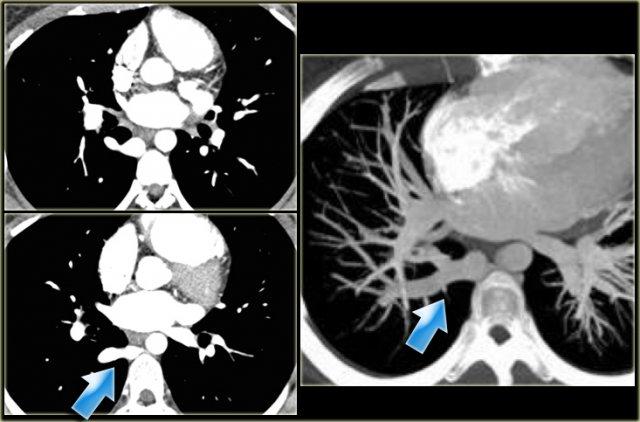

Left Superior Intercostal Vein.

This is an anastomosis between the accessory hemiazygos vein and the left brachiocephalic vein.

It courses along the lateral margin of the aortic arch (‘aortic nipple’).

It is a normal variant and if you look for this structure you will frequently notice it.

Catheters or pacemaker leads may course along left side of mediastinum.

On the left a patient with a left superior intercostal vein.

Notice the ‘aortic nipple sign’.

On the left another example of a left superior intercostal vein.

It courses along the lateral margin of the aortic arch from the the accessory hemiazygos vein to the left brachiocephalic vein.